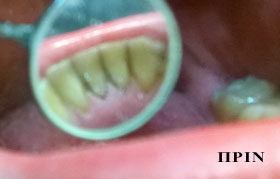

PHOTO GALLERY

:: καθαρισμός